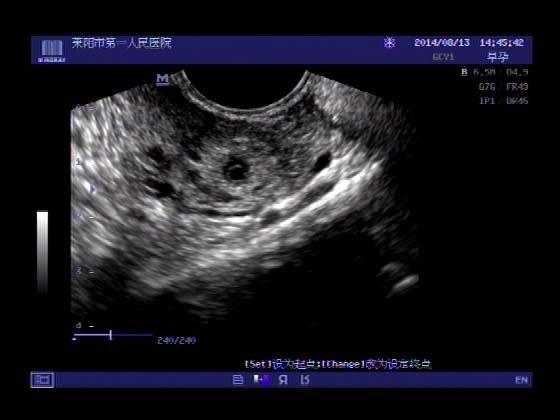

超声入门贴341:宫外孕(阴超的魅力)

女,32岁,停经15天,

一周前在上极医院检查:化验尿HCG阳性,血HCG400多,超声检查问见明显孕囊,让随访。

看见卵黄囊啦~孕囊型的吧?

还能看到卵黄囊,真不错